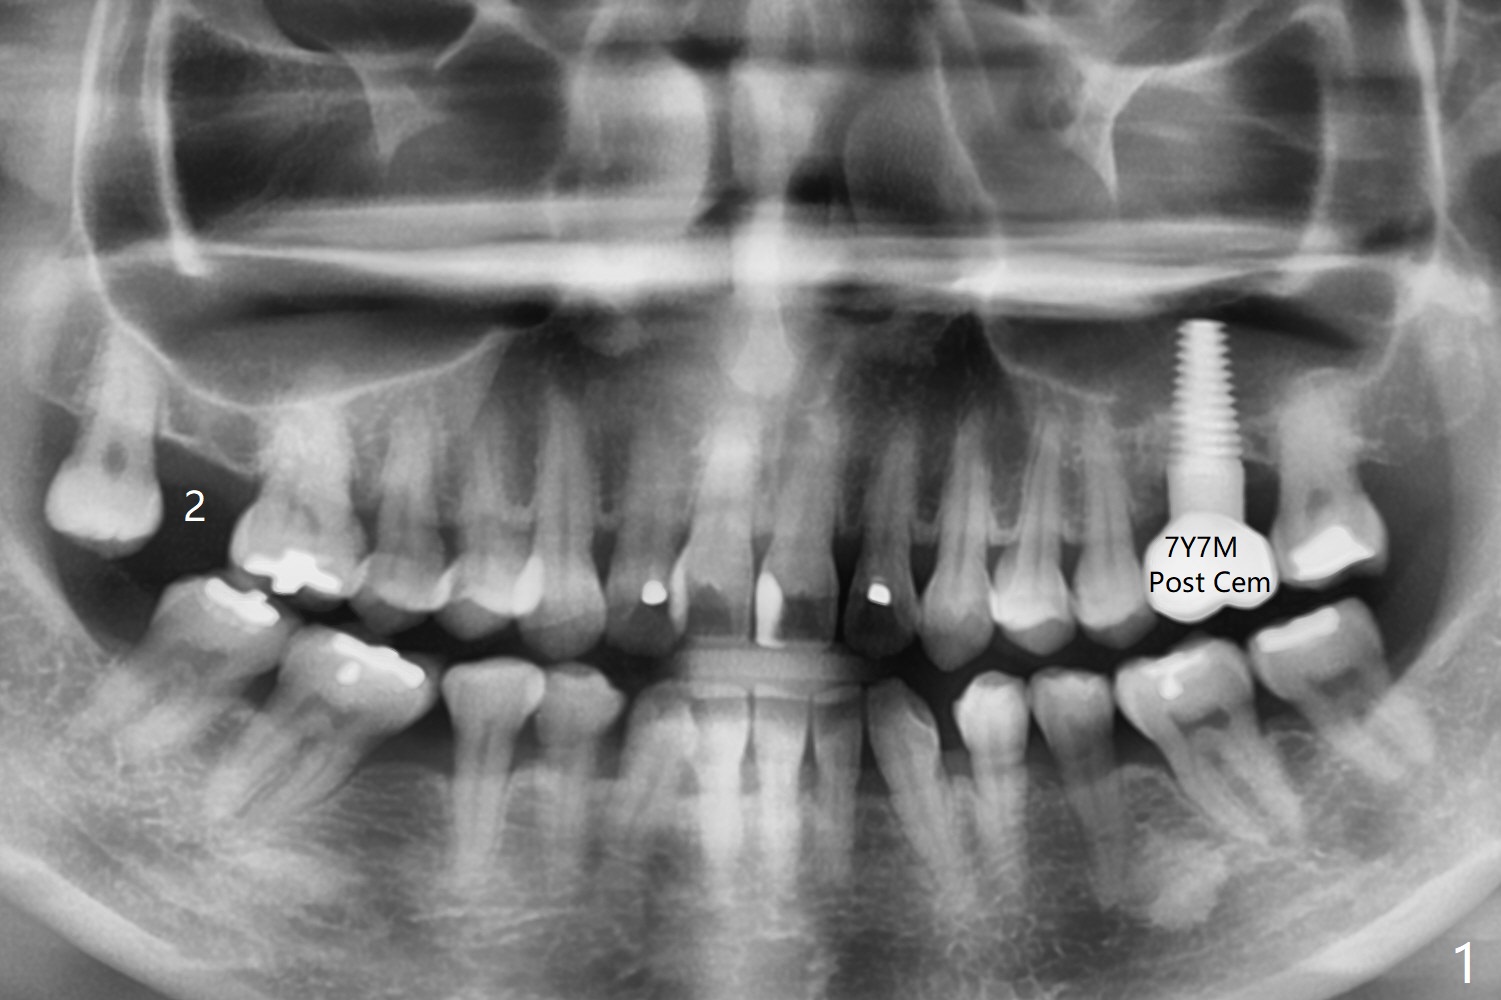

57岁女缺失2号牙多年,八年前14号牙折裂,根管治疗失败,改为即种(徒手),上颌骨骨质高度不足(图一),植体就一定植入上颌窦?近来15号牙又怀疑折裂,不愿接受根管治疗,要求种植。其实14号牙植体植入腭侧牙槽窝,顶端还有骨质,根尖颊侧多个螺纹似乎没有骨质覆盖,但是没有症状。15号牙上端上颌窦膜薄(图三),如果提升时窦膜完整,植入5x8.5毫米植体(图四),否则放置PRF,胶原塞,可以不植骨,植入5x7.3毫米植体(图五)。